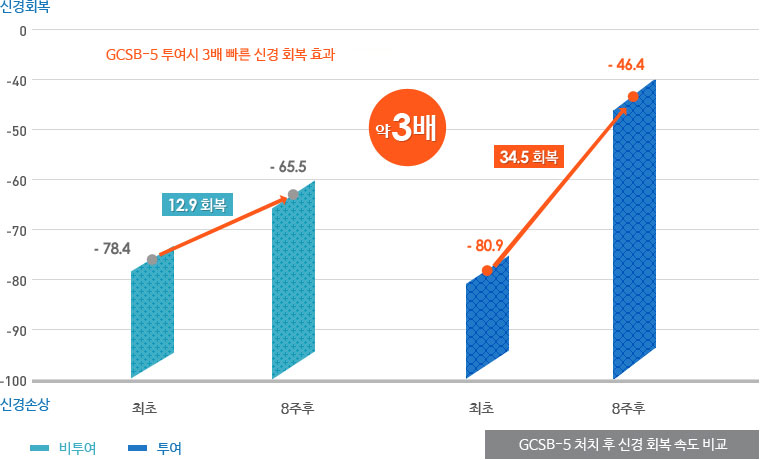

신경 회복 속도 연구 결과

GCSB-5는 신경근회복술에 사용하는 약침의 핵심 성분으로 연골·신경 재생에 효과가 있습니다. GCSB-5의 3배 빠른 신경 회복 효과는 자생척추관절연구소와 성균관대 약대의 공동 연구를 통해 입증되었습니다.

신경재생효과 효능 연구논문 : SCI급 학술지 ‘저널 오브 에스노파마콜로지 (Journal of Ethnopharmacology-Impact Factor 2.322)’ 발표